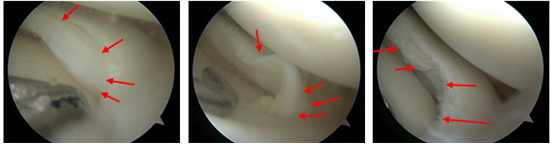

반월상 연골판 파열의 대표적 증상

1. 무릎 관절 부위 통증이 가장 흔하게 나타난다.

2. 연골판이 찢어진 부위를 눌렀을 때 압통이 나타난다.

3. 무릎의 붓기가 쉽게 나타난다.

4. 무릎을 구부렸다 폈다 하는 동작을 할 때 걸리는 느낌이나 날카로운 통증이 느껴진다.

※파열된 조직이 연골 사이게 끼게 되어 걸리는 느낌이 발생하는 것을 잠금(Locking) 증상이라고 합니다.

일부 환자의 경우에는 그 걸림 증상으로 인해 무릎이 휘청거린다는 환자분도 있습니다.

우선 파열의 종류에는 수평 파열, 종파열, 횡파열, 복합 파열 다양하게 나뉠 수 있습니다.